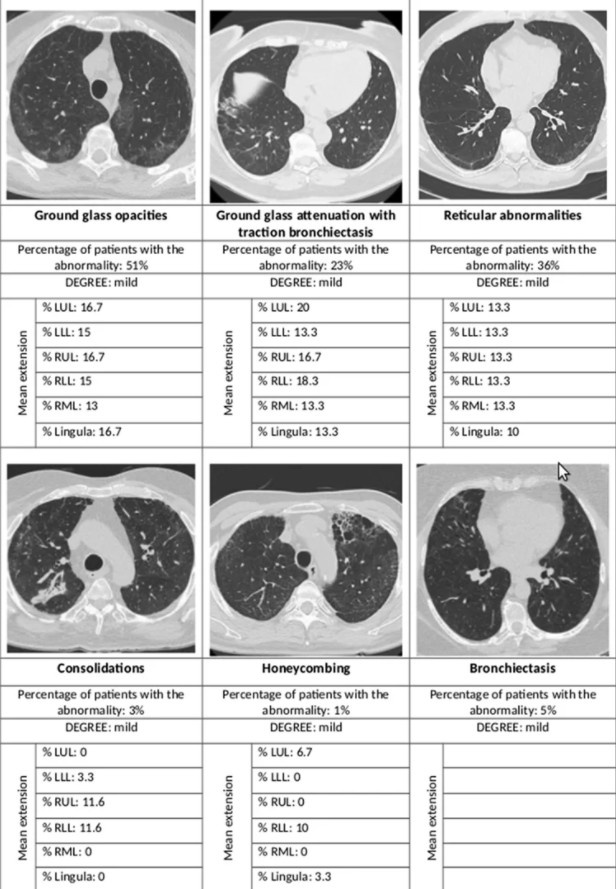

Nghiên cứu mới cho thấy sau một năm khỏi Covid-19, nhiều trường hợp vẫn xuất hiện các bất thường trên phổi như tổn thương kính mờ, giãn phế quản.

Tuy nhiên, nghiên cứu mới đây được công bố trên tạp chí Respiratory Research cho thấy trên hình chụp X-quang của bệnh nhân sau một năm khỏi Covid-19 vẫn xuất hiện các bất thường trên phổi.

Các tổn thương bao gồm tổn thương dạng kính mờ, giãn phế quản, bất thường ở nhu mô và kẽ phổi. Ngoài ra, 1/3 số bệnh nhân từng trở nặng bị suy giảm chức năng phổi, liên tục bị khó thở sau một năm.

Hình chụp X-quang của bệnh nhân sau một năm khỏi Covid-19 xuất hiện các bất thường trên phổi. Ảnh: Respiratory Research.

Khi xem xét ảnh chụp CT phổi, nhóm tác giả phát hiện tổn thương ở nhu mô, tổ chức kẽ. Đặc biệt, hơn 50% bị tổn thương dạng kính mờ, 1/3 có bất thường dạng lưới, dưới 5% bị giảm tỷ trọng không khí trong các nang phổi mỗi bên. 44% bị tổn thương dạng kính mờ kèm theo giãn phế quản.

Trong số những người khuếch tán CO2 bình thường, gần 60% có những bất thường khi chụp CT. Tuy nhiên, khi khả năng khuếch tán CO2 bị suy giảm, tỷ lệ bất thường trên CT lên đến 77%. Con số này cũng tương tự với các tổn thương dạng kính mờ, tương ứng là 45% và 61%. Các bất thường dạng lưới lần lượt xảy ra ở 28% và gần 50% trường hợp.

Từ các kết quả này, nhóm chuyên gia kết luận phổi bị xơ hóa là tình trạng không phổ biến sau khi nhiễm nCoV. Chỉ 1% bệnh nhân có biến chứng này sau 12 tháng kể từ khi xuất viện.